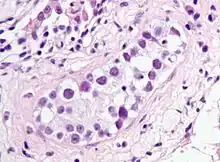

Intratubular germ cell neoplasia. H&E stain.

GCNIS is not palpable, and not visible on macroscopic examination of testicular tissue. Microscopic examination of affected testicular tissue most commonly shows germ cells with enlarged hyperchromatic nuclei with prominent nucleoli and clear cytoplasm. These cells are typically arranged along the basement membrane of the tubule, and mitotic figures are frequently seen. The sertoli cells are pushed toward the lumen by the neoplastic germ cells, and spermatogenesis is almost always absent in the affected tubules. Pagetoid spread of GCNIS into the rete testis is common. Immunostaining with placental alkaline phosphatase (PLAP) highlights GCNIS cell membranes in 95 percent of cases. OCT3/4 is a sensitive and specific nuclear stain of GCNIS.[3]